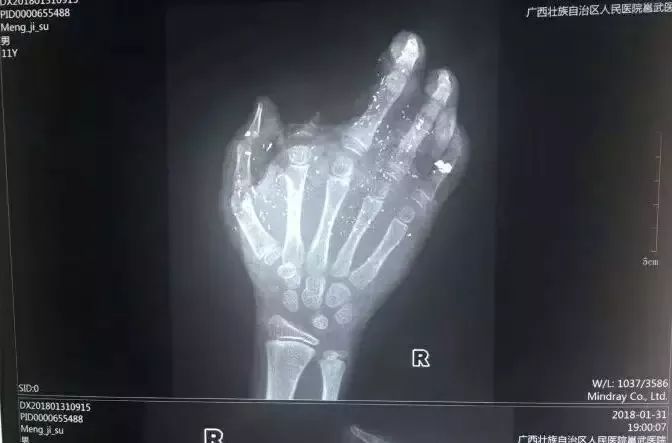

☞2018年1月31日,广西发生一起手机爆炸事件,一名年仅12岁的小男孩手掌被炸得血肉模糊,右手食指被炸没了,拇指、中指、无名指也都炸伤,失去了供血,手掌皮肤被炸得稀烂。原因也是如此!